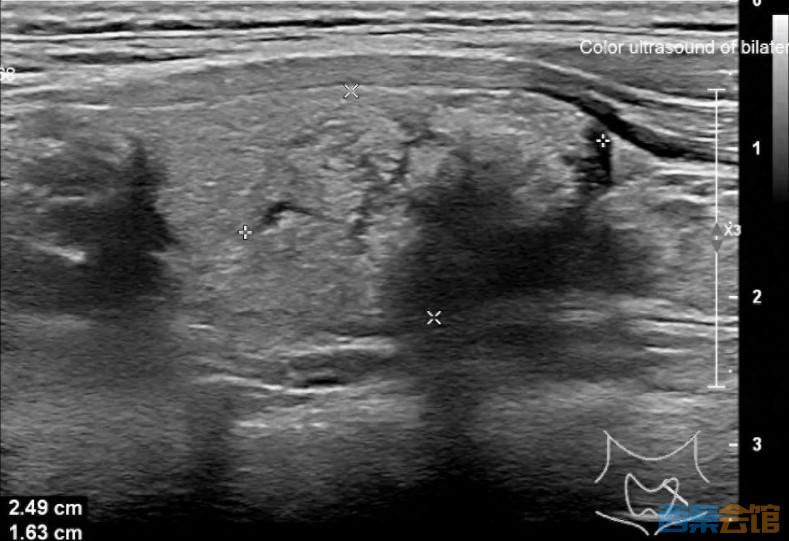

接着,医生安排她做超声波检查,结果显示她的甲状腺左叶有一个2.5公分大的结节、左侧颈部还有一个1公分大的淋巴结。

图:可疑转移淋巴结

根据结节的形态和大小,医生决定进一步进行细针穿刺活检,以排除恶性肿瘤的可能性。不幸的是,活检结果显示结节是恶性的——甲状腺乳头状癌。